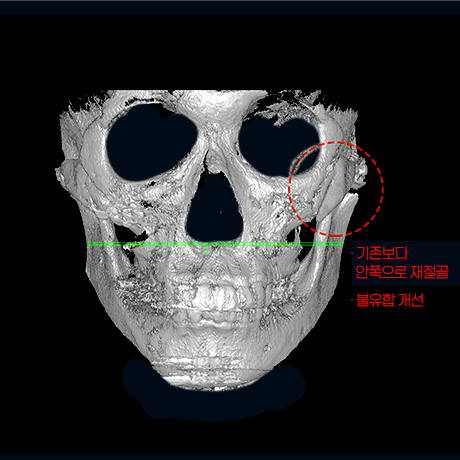

첫 수술 후 45° 광대가 크고

좌우 비대칭 심함

옆 광대뼈 벌어짐 있음